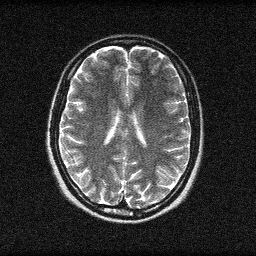

Magnetic Resonance Imaging measures the precession of hydrogen nuclear spins in a strong magnetic field (1.5-7 T). Radiofrequency pulses tip spins away from equilibrium, and gradient fields spatially encode the MR signal into k-space (spatial frequency domain). The image is obtained by inverse Fourier transform of k-space data. Contrast depends on tissue T1, T2, and proton density via the pulse sequence timing parameters.

MRI forms images by exciting hydrogen nuclei with RF pulses in a strong magnetic field (1.5-7T) and measuring the emitted RF signal with receive coils. Spatial encoding uses gradient fields to map signal frequency and phase to spatial position, acquiring data in k-space (spatial frequency domain). The forward model for parallel imaging is y_c = F_u * S_c * x + n_c where F_u is the undersampled Fourier transform, S_c are coil sensitivity maps, and n_c is complex Gaussian noise. Accelerated MRI undersamples k-space (4-8x) and uses SENSE, GRAPPA, or deep-learning (E2E-VarNet) for reconstruction.